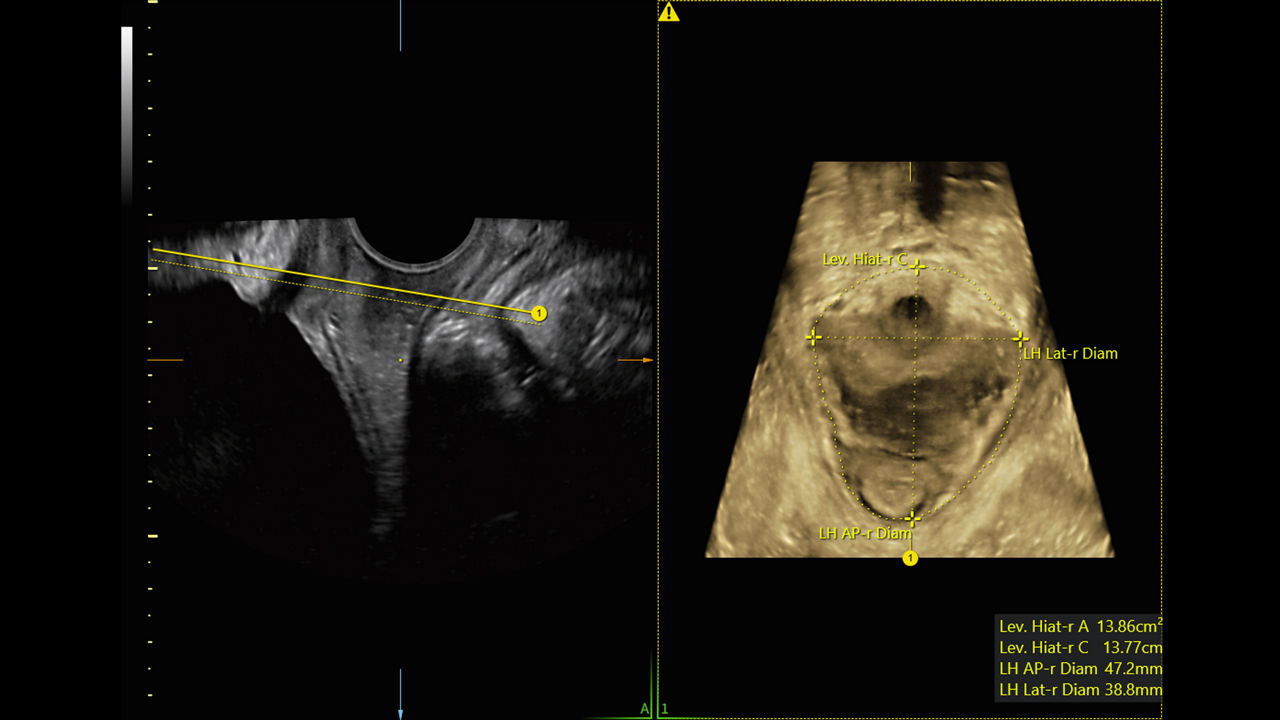

Enhance your workday with leading AI-based technology and progressive tools that simplify and speed up exams. Automate manual tasks and calculations to save time, increase consistency, and improve accuracy.

Segment fibroids with 88% accuracy using Fibroid Mapping